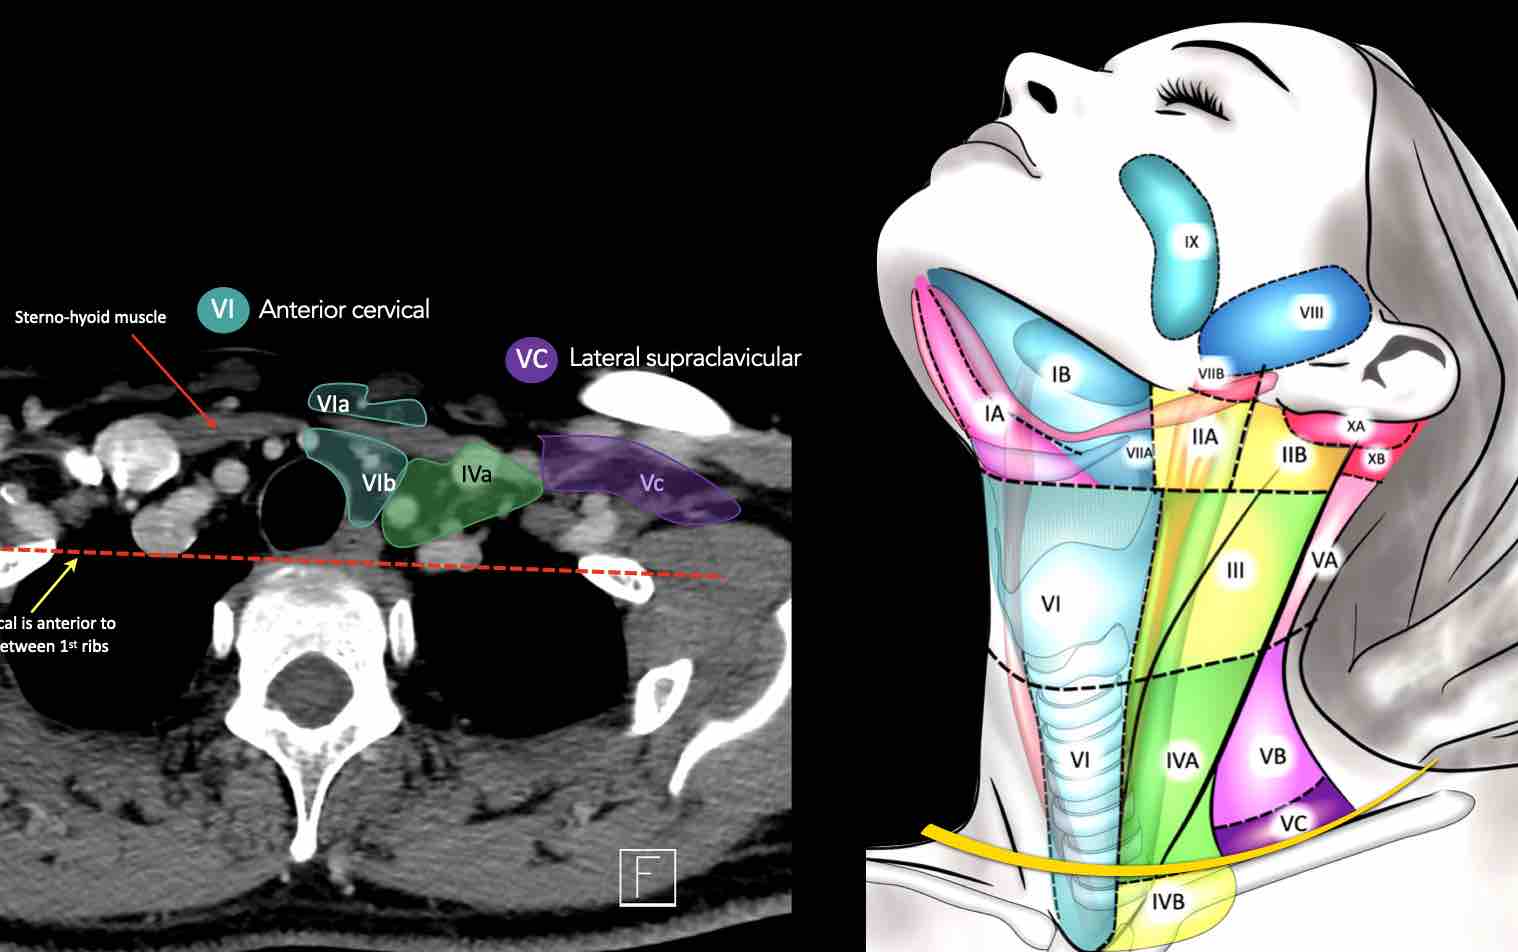

CT Scan Mặt Cắt Ngang (Axial CT)

Các lát cắt CT mặt phẳng ngang tương ứng với hình minh họa tổng quan.

Các lát cắt CT mặt phẳng ngang với hình ảnh chi tiết hơn.

Nhấp vào hình ảnh để phóng to.

Tầng Vc – Hố thượng đòn

Tầng này chứa các hạch thượng đòn bên nằm trong phần tiếp nối của các hạch tam giác cổ sau (tầng Va và Vb) từ các mạch máu cổ ngang xuống đến giới hạn được xác định tùy ý tại vị trí 2 cm phía trên cán ức.

Tầng này tương ứng một phần với vùng được gọi là hố thượng đòn.

Tầng Vc nhận các bạch mạch hướng tâm từ các hạch tam giác cổ sau (tầng Va và Vb) và thường liên quan hơn đến các khối u vòm hầu [1].

VI – Cổ trước

Tầng này chứa các hạch tĩnh mạch cảnh trước nông (tầng VIa) và các hạch sâu hơn bao gồm hạch trước thanh quản, trước khí quản, cạnh khí quản và hạch thần kinh thanh quản quặt ngược (tầng VIb).